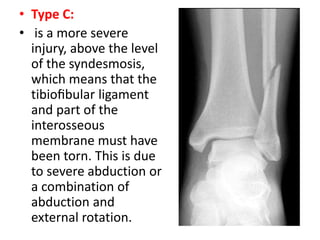

• Type C:

• is a more severe

injury, above the level

of the syndesmosis,

which means that the

tibiofibular ligament

and part of the

interosseous

membrane must have

been torn. This is due

to severe abduction or

a combination of

abduction and

external rotation.

• Type C: •is a more severe injury, above the level of the syndesmosis, which means that the tibiofibular ligament and part of the interosseous membrane must have been torn. This is due to severe abduction or a combination of abduction and external rotation.